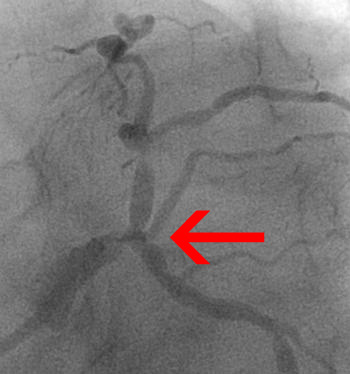

Estimation of the length of that portion of the stenosis that has ≥50% reduction in luminal diameter in the projection where the lesion appears to be the longest. (In case of a bifurcation lesion at least one of the branches has a lesion length of >20mm).